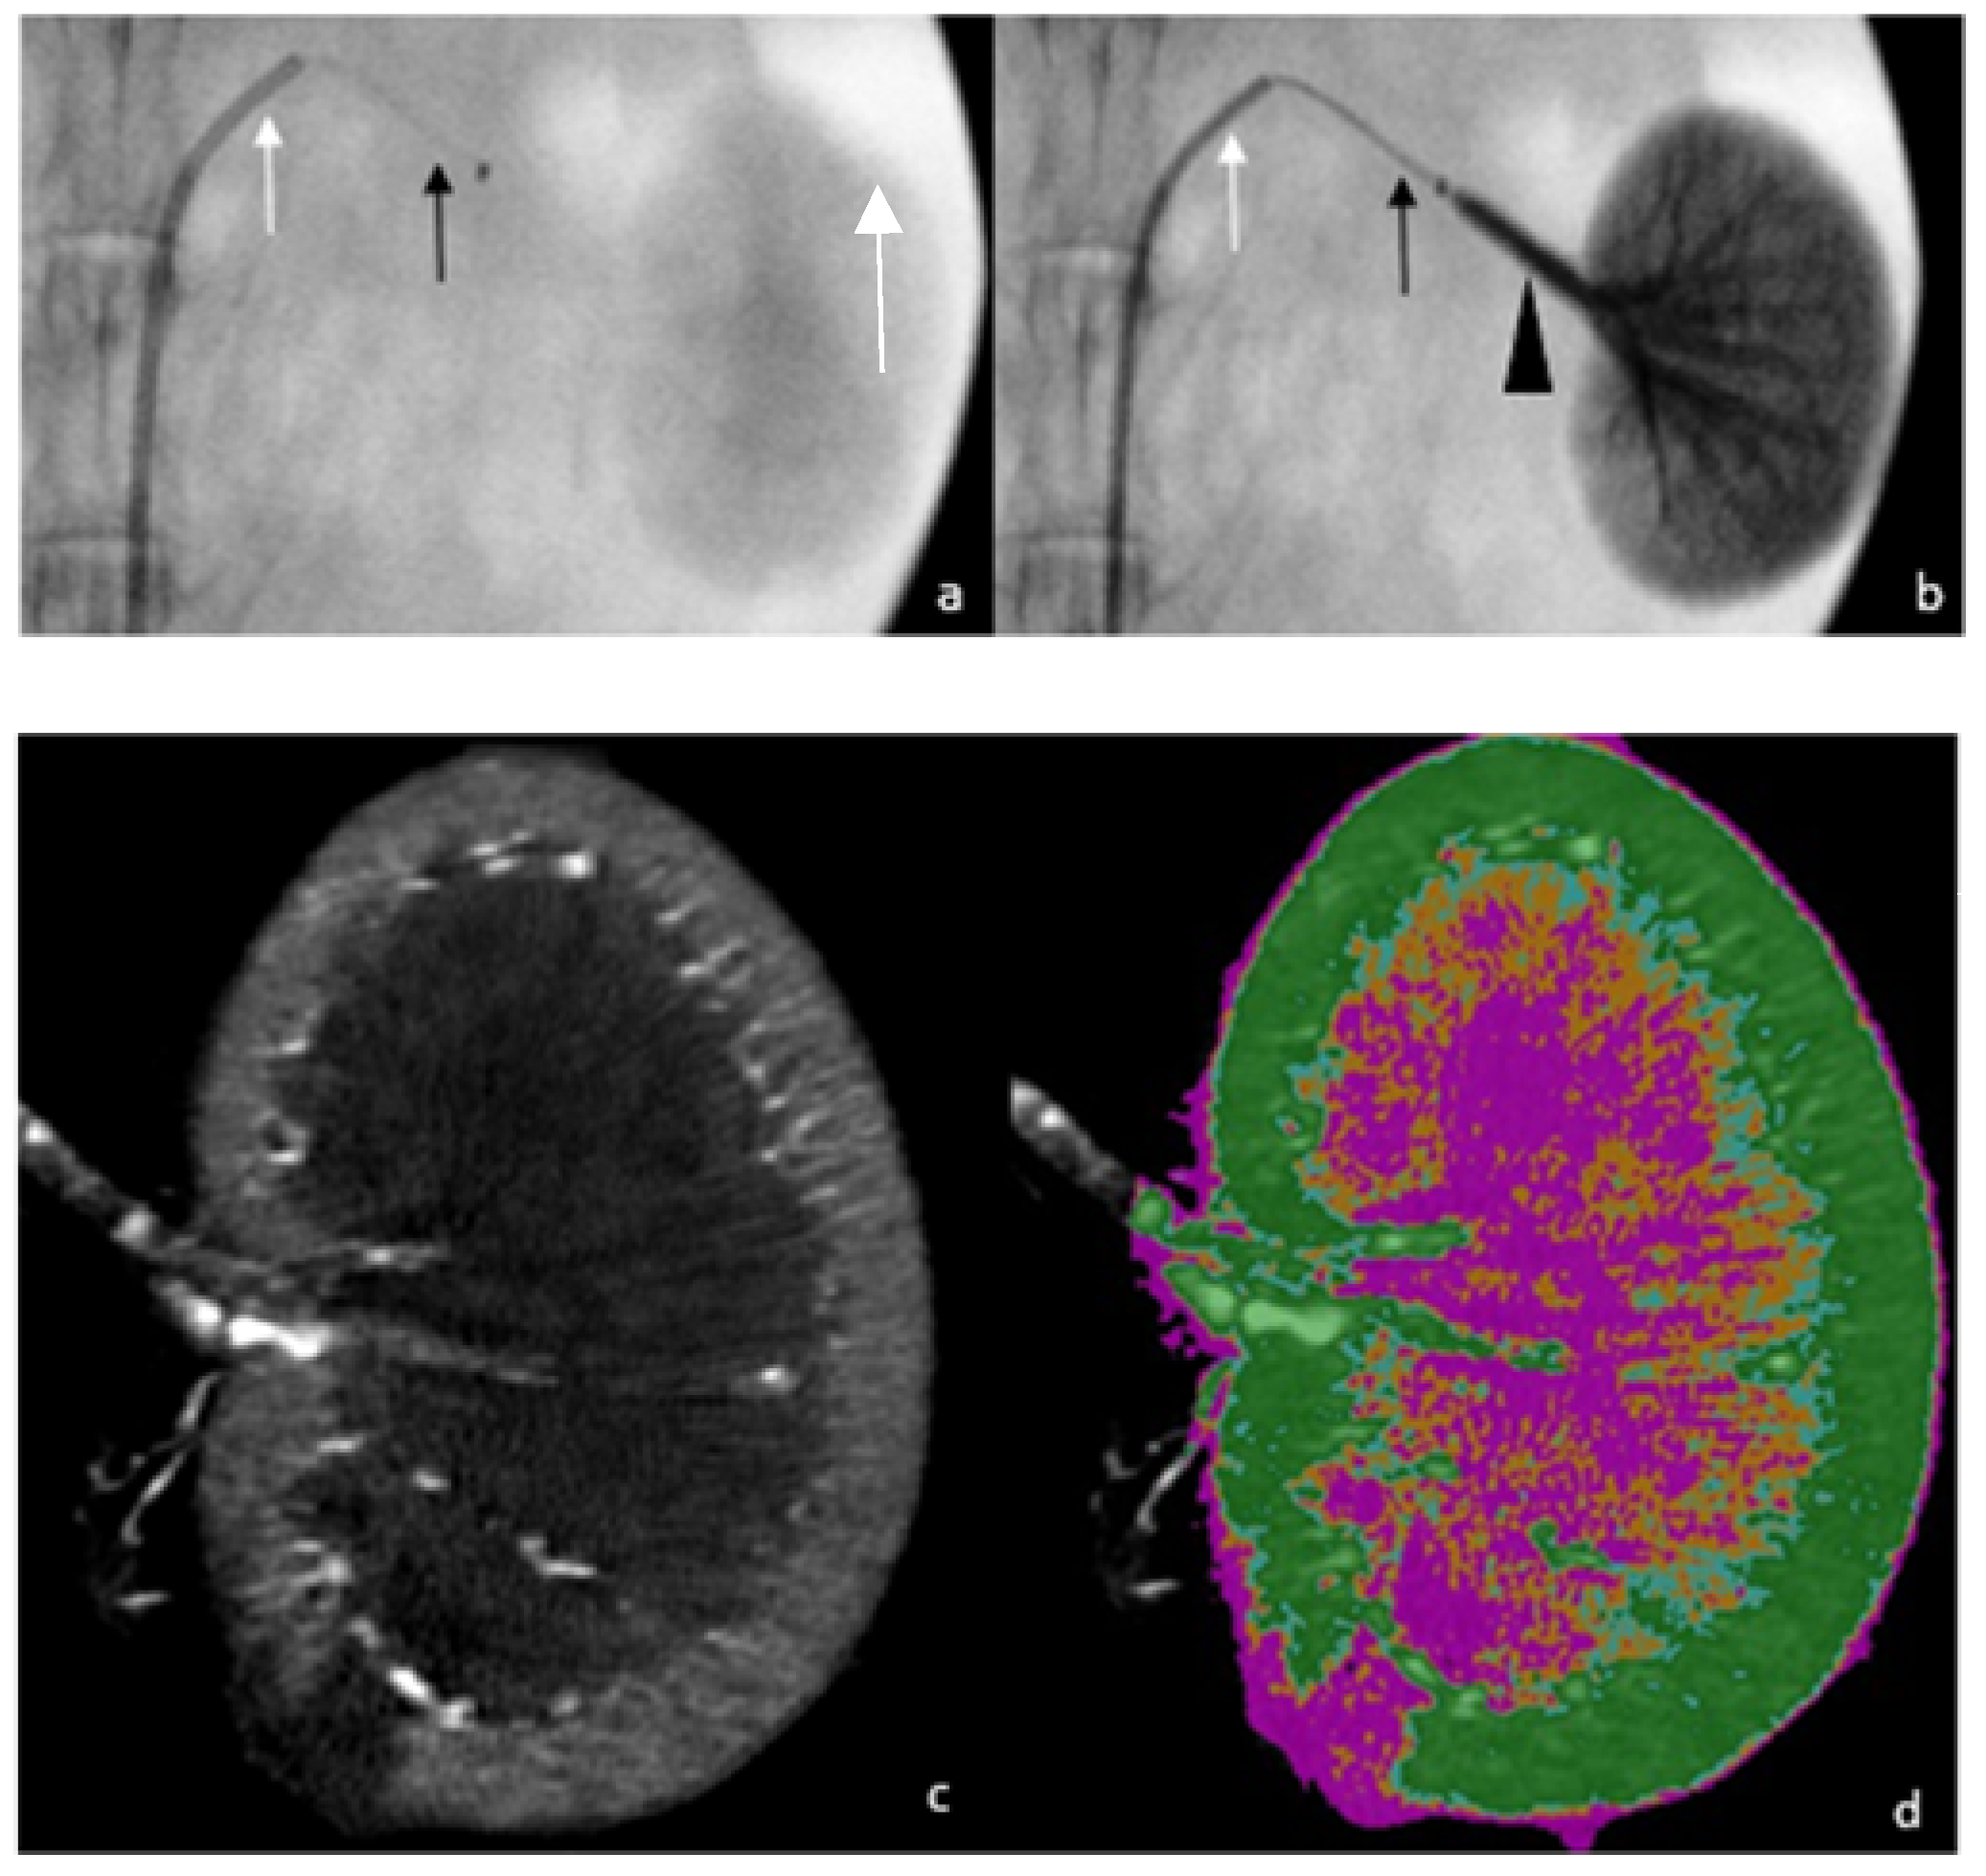

2.1. Experimental Model and Procedure

2.2. Acquisition and Reconstruction Parameters for Micro-CT

2.3. Data Analyses and Outcomes

2.3.1. Objective Outcomes

2.3.2. Subjective Outcomes

2.3.3. Image-Quality Criteria